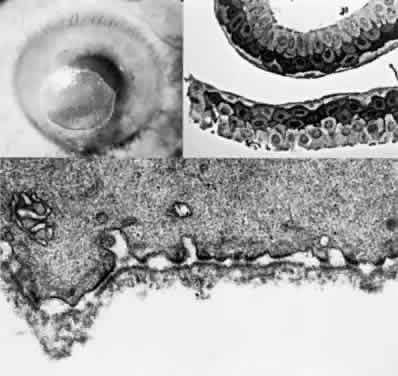

OCULAR FINDINGS. One of the few truly diagnostic and pathognomonic physical signs in clinical medicine is a Kayser-Fleischer corneal pigment ring found in patients with Wilson's disease (Fig. 5).This ring is recognized as a golden-brown, ruby-red, or green band of 1.0 to 3.0 mm, starting at the limbus but at the level of Descemet's membrane.53 The color of the ring is presumably caused by scattering and reflection of incident light and by photointerference effects created by the layers of copper granules. Such variables as size, shape, and unit density of the granules may account for the different appearances of the Kayser-Fleischer ring. The course of the Kayser-Fleischer ring has been well documented.54,55 The site of earliest pigment deposition is an arc in the superior periphery of the cornea from the 10- to 2-o'clock meridian. The arc spreads slowly toward the horizontal plane and gradually broadens. Later in the progression of the ring formation, a band appears inferiorly as a crescent stretching from the 5- to 7-o'clock positions. In time, the two arcs meet. With treatment, the sequence of events is reversed, and after the copper has reabsorbed, a pitted or beaten silver pattern may become apparent at the previous site of the ring. This is an indication that treatment has produced a negative copper balance.49 Decreased visual acuity is not a problem. Rarely, copper is deposited in the crystalline lens, giving an anterior subcapsular “sunflower” cataract.

Fig. 5. Wilson's disease. Kayser-Fleischer peripheral corneal ring. Copper pigment at level of Descemet's membrane.

PATHOLOGY. Electron microscopic, x-ray energy spectroscopic, and atomic absorption spectroscopic studies of the Kayser-Fleischer rings have revealed electron-dense granules rich in copper and sulfur in both the peripheral and the central region of the cornea, but more abundantly at the periphery. The association of copper with sulfur suggests that a sulfur-containing moiety functions in binding copper.59